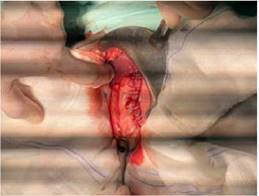

Indagando a la progenitora, esta relata que desde hace dos años la paciente presenta cambios de conducta caracterizado por rasgo esquizoide, sugestivo de patología psiquiatrica4. Al examen físico, paciente en regular estado general, peso 43kg, talla de 173cm y un IMC 15. Cardiopulmonar estable, abdomen: plano, RHA(+), se palpa masa a nivel de epigastrio, no doloroso a la palpación. A su ingreso se le realizo laboratorios que reportaron: Albumina 2.7 gr/dl, proteínas totales 4,6 gr/dl, glicemia 68, glóbulos blancos 6820, glóbulos rojos 4350000, hemoglobina 9,3g/dl, VCM 63,5fL, Hematocrito 27,6. Tomografía abdominal donde se evidencia imagen en miga de pan que ocupa casi en su totalidad la luz gástrica hasta la 3ra porción del duodeno. E ingresa al servicio de cirugía con los diagnósticos: tricobezoar gigante, anemia moderada y desnutrición. Durante su internación se le realizo, como indican las diferentes publicaciones, una endoscopia digestiva alta que reporta: tricobezoar gigante, lesión elevada de duodeno a descartar neo (histopatología reporto, cambios hiperplásicos, signos de ulceración y cambios inflamatorios) y se le indico nutrición parenteral, antibióticos, transfusión de 2 concentrado de glóbulos rojos y valoración por hematología y psiquiatría, este último para realizar un manejo más integral del paciente5. Hematología le diagnostica anemia ferropénica severa, e indica hierro sacarato y psiquiatría diagnostica tricotilomanía y síndrome ansioso depresivo e indica alprazolam. Al séptimo día de internación una vez mejoradas las condiciones generales de la paciente, se decide su intervención quirúrgica, se realiza una laparotomía exploradora, gastrotomía, extracción de tricobezoar y rafia de ulcera gástrica, gastrorrafía y lavado y drenaje de cavidad y como hallazgo transquirurgico además del tricobezoar gastroduodenal se evidencia una ulcera en la cara posterior del cuerpo gástrico. Se decide la conducta precisamente por ser un tricobezoar gigante, que no sería resuelto por endoscopia, además se podría dar solución a la ulcera gástrica en la laparatomia; al ser un cirugía limpia - contaminada y por el tamaño de pieza que se iba a extraer se opto por la vía convencional.